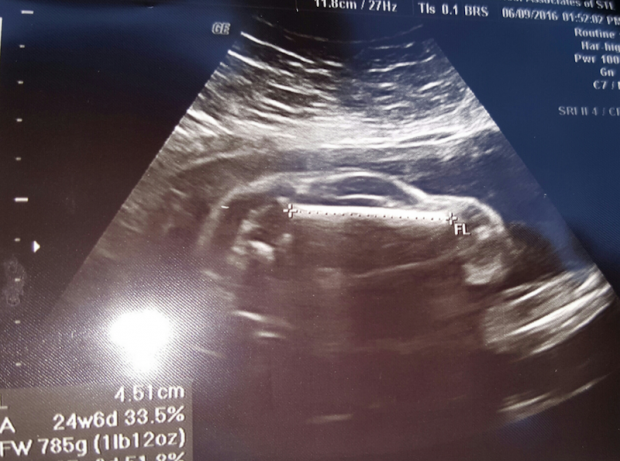

Asta deoarece, pe monitorul ecografului se putea observa ceva ce părea a fi… o maşină, nu un copil. Din cauza poziţiei în care stătea, bebeluşul a reuşit să le aducă zâmbetul pe buze nu doar părinţilor, ci şi medicilor.

Imaginea, încărcată pe Reddit de către tatăl copilului, cu descrierea „Soţia mea este însărcinată cu o maşină”, a strâns sute de reacţii.